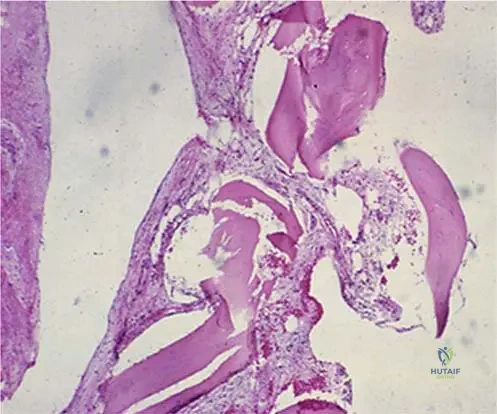

Question 11

A bone biopsy from a patient with suspected Gorham's disease reveals the microscopic features shown in the image, characterized by cavernous angiomatous spaces. What is a key characteristic of the endothelial cells lining these spaces in Gorham's disease?

View Answer & Explanation

Correct Answer: C

Rationale: The text accompanying Fig. 8.63 explicitly states, "Endothelial cells show no cytological atypia." This benign nature is a defining feature of Gorham's disease. Main Distractor: Option A, they exhibit significant cytological atypia, is the direct opposite of the described pathology and would suggest a malignant vascular tumor rather than Gorham's disease.

Question 12

A pathologist is reviewing a bone biopsy from a patient with extensive osteolysis. The microscopic findings include vascular changes and cavernous angiomatous spaces. To support a diagnosis of Gorham's disease, the pathologist would specifically note the absence of which feature?

Correct Answer: B

Rationale: The text states, "Microscopic examination shows varying amounts of vascular changes without reactive bone formation." The absence of reactive bone formation is a key diagnostic characteristic. Main Distractor: Option A, endothelial cell proliferation, is incorrect because vascular changes and angiomatous spaces imply endothelial cell proliferation, which is a *present* feature, not an absent one.